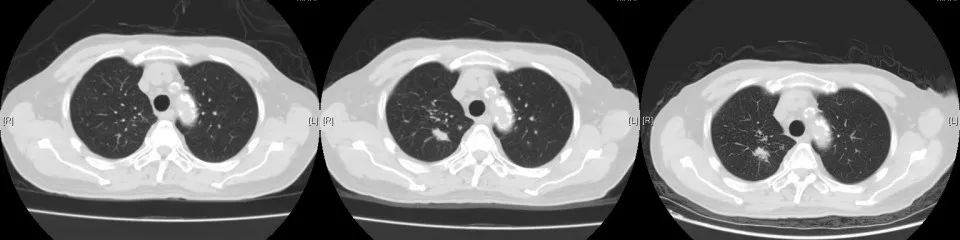

2020年3月复查,病灶再次进展,参考前次基因检测结果,结合临床情况,即开始给予口服吡咯替尼80mg每日一次,2020年4月25因心梗住院治疗。停药约2周。复查示原转移灶稍增大,考虑是否与停药有关,故继续维持吡咯替尼治疗。期间多次复查,病情稳定。局部考虑缓慢进展可能。但综合考虑临床情况,仍继续维持原方案治疗。

CT变化: